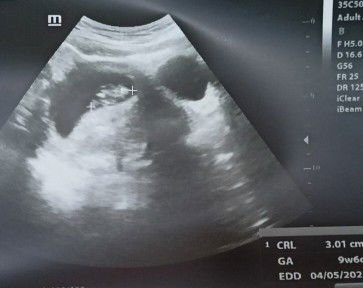

Scan 9minggu

Salam. Nak tanya , usia baby 9 minggu. Baru scan and xnmpk jelas bentuk baby. Bentuk kantung pun mcm tu kira normal ke? #firstbaby

x boleh nampak dengan jelas sis..mungkin kena tunggu minggu seterusnya :) harap sis banyakkan bersabar, insyallah baby sis sihat dan kuat mcm mama dia :)